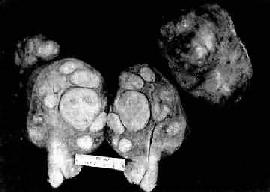

图13-7 子宫平滑肌瘤

多个肌瘤结节,位于肌壁内、粘膜下及浆膜下,境界分明,宫腔受挤压呈裂隙状

肉眼观,肌瘤可以生长在子宫任何部位,常位于子宫壁内(肌层内肌瘤)、浆膜下(浆膜下肌瘤)或粘膜下(粘膜下肌瘤)。可单发或多发,常为多个,其数目多少不等,常见为数个、乃至十数个或数十个,称多发性平滑肌瘤。肌瘤的大小可极为悬殊,小的在显微镜下才可检见,大的如成人拳大或更大,甚至可充满整个腹腔。肌瘤多呈球形或融合成不规则形,质较硬,界限明显,但无明显包膜(图13-7)。切面上,瘤组织常呈灰白色,编织状或旋涡状,当肌瘤生长较快或供血不足时,可发生各种继发性改变,如玻璃样变、粘液变、囊性变、水肿及出血、坏死等。